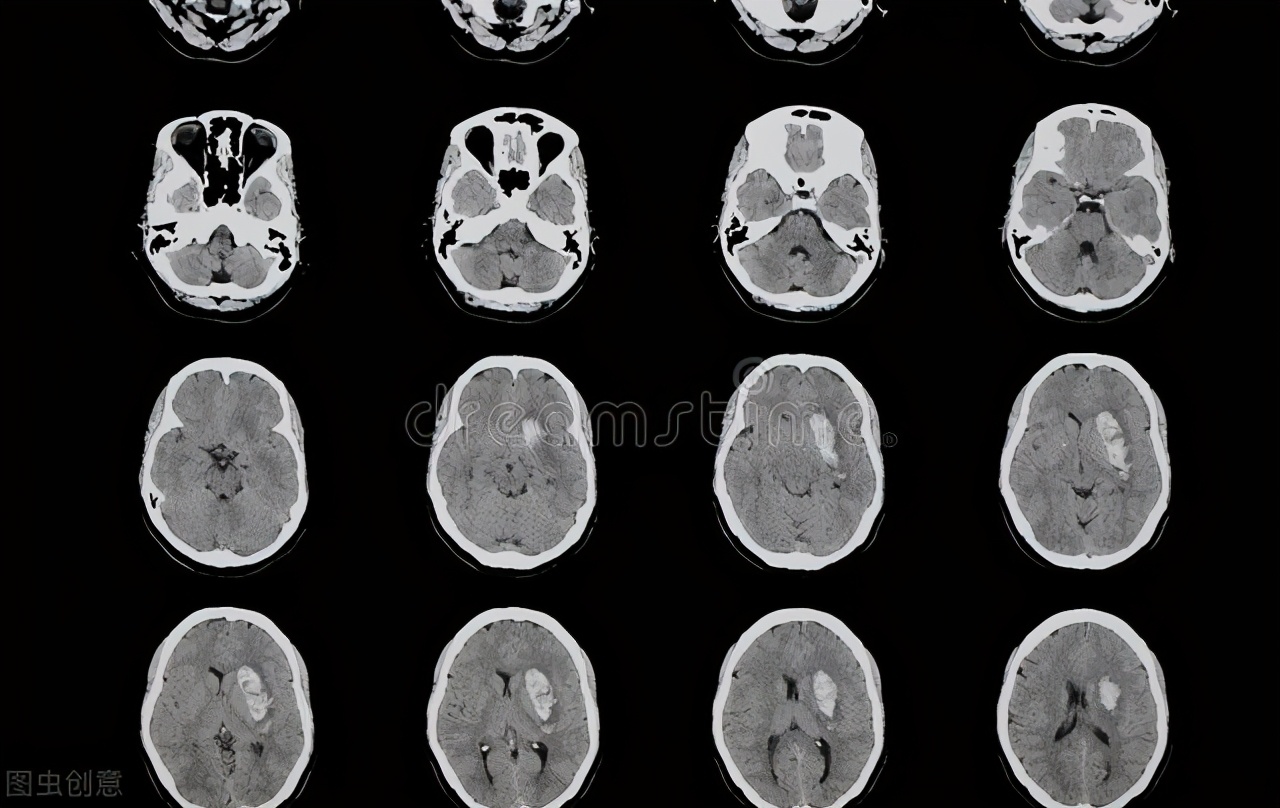

四、颅内占位

上面说的几种头痛虽然折磨人,但总的来说还属于可控可治的范围,要说慢性头痛中最怕的就是发生了颅内占位。

许多脑部的肿瘤一开始并不一定就会头痛,因为大脑中有一定的空闲位置,小的肿块对脑组织压迫较轻,如果平常精神很好,就很难感受到这种轻微的异常,或是仅有轻度的钝痛。

随着肿块逐渐增大,肿瘤直接牵引、伸展或挤压脑血管,并对脑组织产生压迫,大脑的血液和脑脊液循环出现障碍,颅内压力日益增高,头痛也就日渐加重。

由于压迫部位不同,颅内占位的头痛会出现多种表现,例如:

1. 慢性逐渐加重,并出现颅内压增高的症状,如呕吐,眩晕;

2. 轻、中度头痛在咳嗽、打喷嚏、摇头、俯身时加重;

3. 压迫不同神经使可出现头痛伴随精神症状,如嗜睡、谵妄等,偶尔也可能出现伴有视力或视野问题,需要与青光眼鉴别。

慢性头痛病因多,以上这几种只是头痛常见的大类,在治疗时需要明确鉴别。对于长期且逐渐加重的头痛,我们应当引起重视,及时到医院神经科就诊,进行脑部的影像检查或脑电图检查、排除颅内占位、异常放电的可能。如果头痛伴随颈椎不适,可通过X线、CT或MRI等检查排查颈椎病。